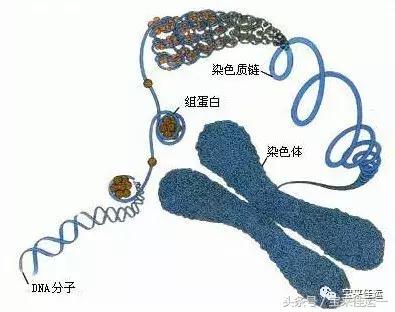

染色体是细胞核中载有遗传信息的物质,人类的性染色体是23对染色体的其中一对组成,拥有X和Y染色体各一个的个体是男性,拥有一对X染色体的个体是女性。